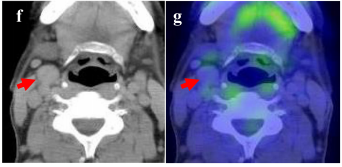

咽部转移病灶切除术后两年,再次发现颈部淋巴结转移,患者进行颈部淋巴结清扫术。

移植肝随后发生了3次肝内复发,患者接受TACE以及局部消融治疗,效果良好。

图6. 患者淋巴结转移